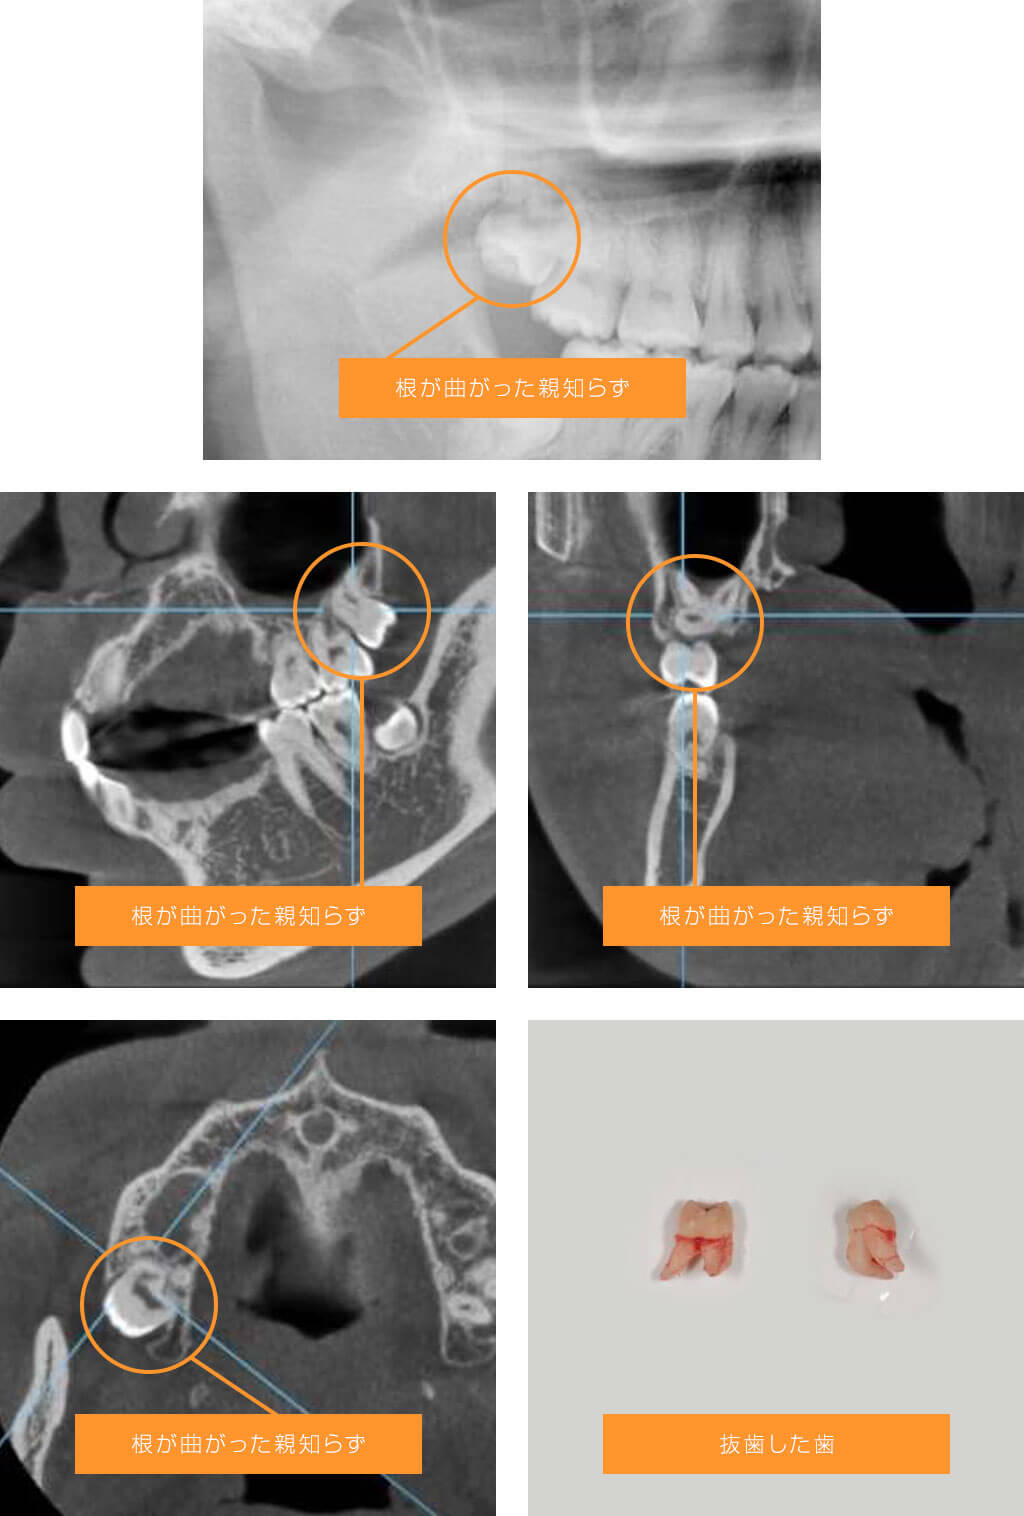

症例2 極端に根が曲がっている左上の親知らずの場合

正元のコメント

上顎の親知らずは時に根の形態が複雑になっています。通常のX線写真でもおおよその根の形態は把握できますが、この方は下の親知らずが神経と近くてCTを撮影していました。CTでは思ったよりも根が曲がっており、抜歯の際に根が折れるリスク、上顎洞に穴が開くリスクを説明した上、抜歯に同意が得られたので、抜く方向を工夫して抜歯しました。根も折れず、上顎洞にも穴も開かずに抜歯できました。

患者さまの感想

親知らずが何度か痛くなったので、抜歯のため口腔外科専門医を探してしょうげん歯科医院を受診しました。上の親知らずについて、色々と説明をうけましたが、ただの抜歯でもリスクがいくつもあることを知りました。抜歯後は痛みもほとんどなく、満足しています。

処置時間と費用

処置時間:約30分(麻酔時間含め)

費用:約4,000円(パノラマ費用含む)*CTを撮影しない場合です。CTの費用は約3500円です。

リスクと副作用

術後に腫れや痛みが生じ、時に痛みがひどい場合があります。上顎の奥歯は抜歯すると抜歯した穴が顎の内部空洞(上顎洞)とつながる場合があります。根が曲がった歯は抜歯の際に根が折れて骨の中に残ってしまう場合があります。